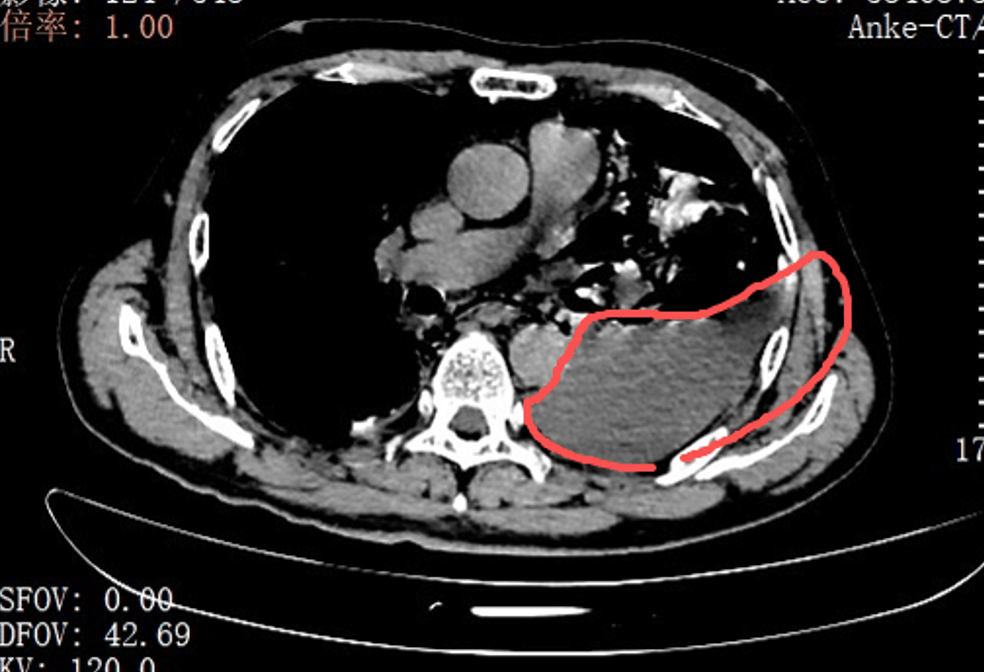

当天(tian),手术团队为(wei)张叔实施了胸腔镜下食道修补微创手术。打开胸腔的那一刻,在场的医(yi)护人员(yuan)都愣(leng)住了:全部左侧胸腔里,满是叉烧包的菜叶子、食物(wu)残渣,混着脓液和消化(hua)液,到处都是。

红圈(quan)区域是食物(wu)残渣、消化(hua)液破入食管

手术团队拿着吸引(yin)器,一点点清理、冲洗,花了很长时间(jian)才将胸腔里的每一点食物(wu)残渣都清清洁。随后,团队找到了食道下段那道长达10公分的裂口,用可吸收线谨慎翼翼地完成了分层修补。